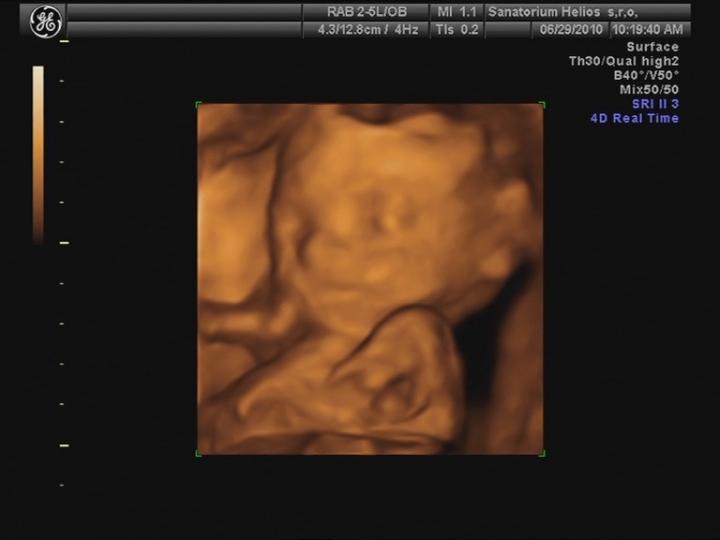

25.5. jsme vstoupili do 5. měsíce .... nečekaně se to pohlo 🙂